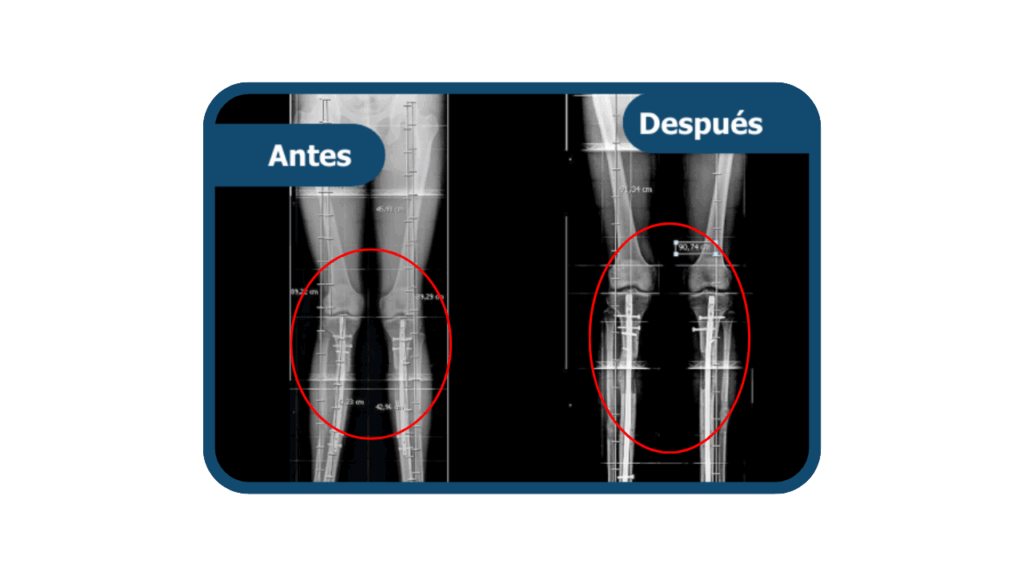

Genu varo

El Genu varo es una deformidad ósea en la que las rodillas se desvían hacia afuera, generando una separación entre ellas y sobrecarga en la articulación. Puede causar dolor, desgaste articular y dificultad para caminar. En Clínica Arthrosalud tratamos con muchos casos y logramos darle la alineación correcta a nuestros pacientes.

El tratamiento depende del grado de la deformidad. En casos leves, se maneja con terapia física y control médico. En casos moderados o severos, se corrige mediante una cirugía llamada osteotomía, que permite realinear el hueso y restaurar la correcta posición de la pierna, mejorando la función y previniendo el desgaste articular.